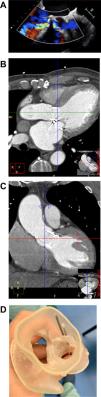

We present the case of a 73-year-old man admitted for heart failure due to severe PVL of a bioprosthetic aortic valve (Figure 1A). After cardiac computed tomography (Figure 1B and C), a three-dimensional (3D) printed model of the heart (Figure 1D–F) was made and the PVL was closed in a patient-specific simulation with three Amplatzer Vascular Plugs (AVP) (5-mm AVP III 14, 5-mm AVP III 10 and 5-mm AVP II). The procedure was replicated in the patient without significant residual regurgitation on color 3D transesophageal echocardiography (Figure 1G).

(A) Transesophageal echocardiography showing severe paravalvular leak (PVL) of the bioprosthetic aortic valve; (B and C) cardiac computed tomography images used to construct the three-dimensional (3D) printed models of the heart; (D–F) 3D printed model of the heart with simulation of PVL closure using three Amplatzer Vascular Plugs (AVP) (5-mm AVP III 14, 5-mm AVP III 10 and 5-mm AVP II); (G) fluoroscopy image of the procedure.